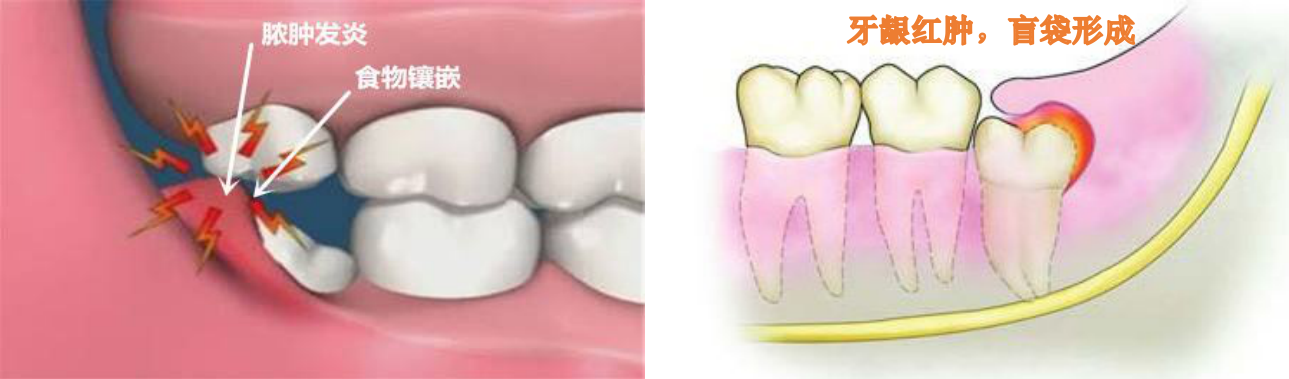

随着人类的饮食的精细,颌骨逐渐变小,而牙齿大小没有明显变化,这就导致了牙量大于骨量,所以智齿因为生长空间的受限往往萌出受阻或异位生长,甚至还会挤压前面的第二磨牙,这就会造成智齿区牙龈肿痛、邻牙损伤,颞颌关节病,并成为牙源性囊肿及肿瘤、面部肿胀、面部间隙感染、张口受限等不适症状,严重的可能会引起发烧等全身症状。

拔:若是有智齿反复肿痛,甚至导致面部肿胀、张口受限等,建议消炎后拔除。

拔:若是智齿本身有龋坏,或引起邻牙龋坏,一般也建议拔除。

拔:当智齿位置不正挤压导致前方第二磨牙龋坏或者牙齿松动,一般建议先行拔除智齿后酌情治疗第二磨牙。